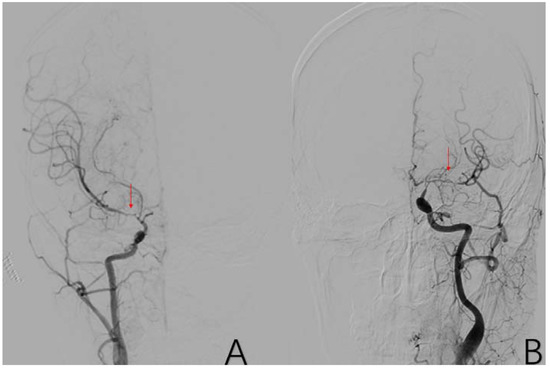

2.3.9. Factor 4 PCA Anomaly

2.3.10. Factor 5 Posterior Circulation Compensation

2.3.11. Factor 6 Unstable Compensation